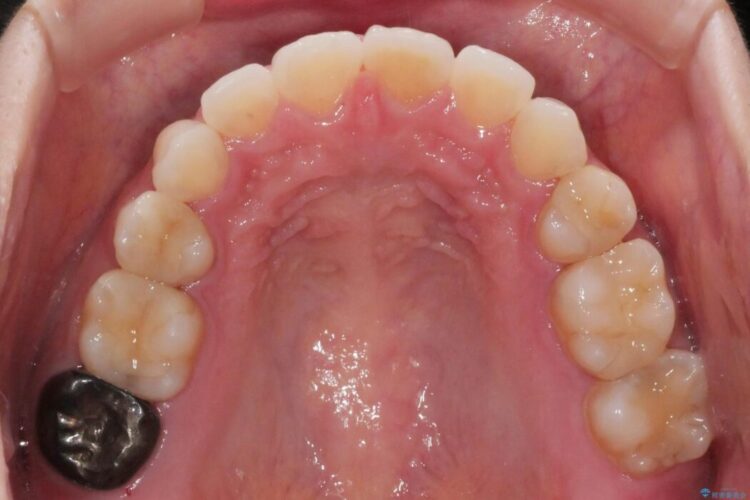

【20代女性】矯正治療後の後戻り

- 患者様:20代女性

- 治療期間:1年

- 矯正装置:審美装置

- 概算治療費:66万円

抜歯矯正後の後戻りについてご相談にいらした患者様です、

後戻りの程度としては軽度なので、治療期間としては短く終えることが出来ました。

前歯の正中線も改善され大変満足していただきました。